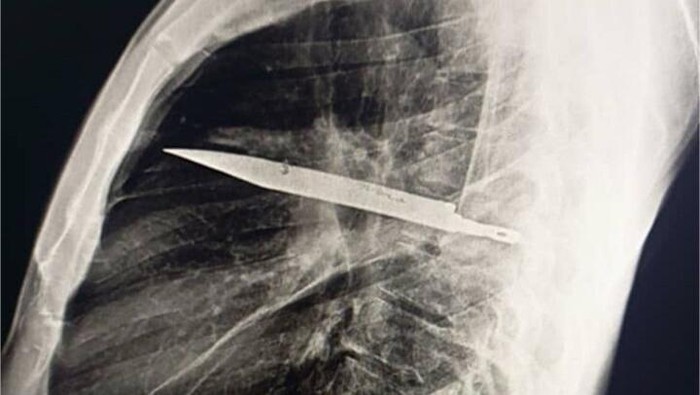

“Pencitraan awal dengan radiografi dada lateral menunjukkan adanya benda logam yang tertahan di bagian tengah toraks, dengan kekeruhan di sekitarnya yang kemungkinan merupakan hematoma terlokalisasi kronis atau yang sudah sembuh, atau fibrosis pascatrauma, yang merupakan sekuel dari luka tusuk pasien,” tulis para dokter. (Foto: Journal of Surgical Case Reports).